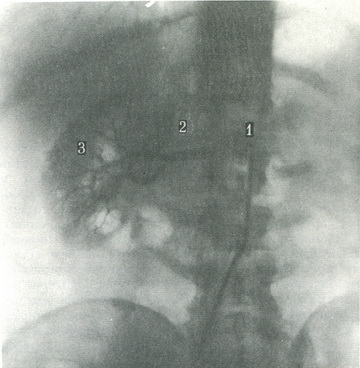

Артеріограмми ниркових судин. Контрастну речовину через катетер вводять в аорту або безпосередньо в ниркову артерію. Подібні знімки, як правило, виконують при підозрі на склероз, звуження або аномалію нирки (рис. 407).

407. Селективна артериограмма правої нирки. 1 - катетер; 2 - права ниркова артерія; 3 - внутрипочечные артеріальні гілки.